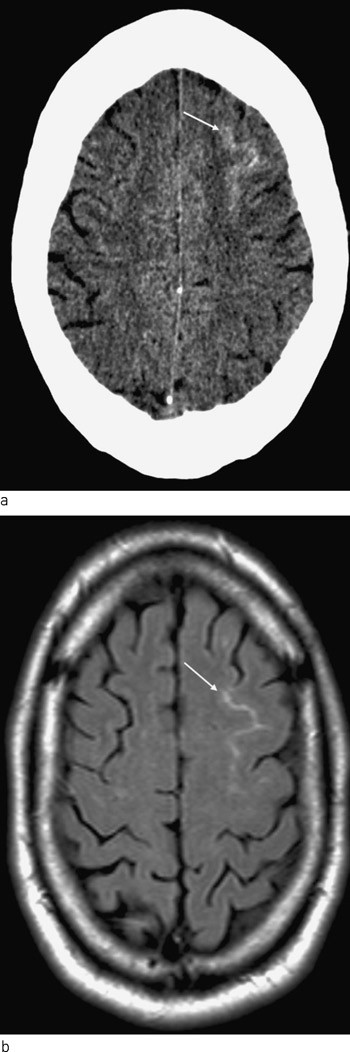

Det ble startet utredning med henblikk på bakenforliggende systemisk vaskulitt. De vaskulitter som hyppigst affiserer sentralnervesystemet, er Behçets sykdom og polyarteritis nodosa. Også vaskulitter assosiert med antinøytrofile cytoplasmaautoantistoffer (ANCA), som Wegeners granulomatose, mikroskopisk polyangitt og Churg-Strauss’ syndrom, samt kryoglobulinemiassosiert vaskulitt kan en sjelden gang affisere hjernen. Det ble gjort CT thorax og CT bihuler samt abdominal angiografi – med normale funn. Undersøkelser på antimyeloperoksidase (MPO) og PR-3-ANCA var negative, det samme gjaldt kryoglobuliner. Inflammasjonsmarkører og hematologisk status var normale, uten eosinofili. Kreatininverdien var normal og urinstiks negativ. Antinukleære antistoffer (ANA), C3, C4, lupusantikoagulant var negativ, mens det var grenseverdi for antikardiolipinantistoffer. Det ble heller ikke funnet holdepunkter for systemisk lupus erythematosus, Sjögrens syndrom eller dermatomyositt. Biopsi fra tykktarm viste kronisk betennelse med fokal kryptitt uten vesentlig begercelletap, kryptabscesser, granulomer eller ulcerasjoner. Intraarteriell cerebral angiografi ble utført på dag 4 og viste utbredte områder med kaliberveksling i både fremre, midtre og bakre hjernearterie bilateralt (fig 2).

Med utgangspunkt i disse funnene ble det vurdert om det kunne foreligge en isolert cerebral vaskulitt. Ved ny gjennomgang av sykehistorien kom det frem at pasienten det siste halvåret hadde hatt flere episoder med forbigående mindre intens hodepine i forbindelse med seksuell aktivitet/orgasme. Det viste seg også at han tidligere hadde brukt amfetamin, at han røykte hasj regelmessig og hadde røykt hasj timen før den aktuelle hodepinen debuterte. Ved revmatologisk tilsyn ble det reist spørsmål om det kunne dreie seg om reversibelt cerebral vasokonstriksjon-syndrom. I litteraturen er det beskrevet flere former av dette syndromet under et mangfold av eponymer og navn. Ettersom sykehistorien og funnene hos pasienten var forenlig med tilstanden, valgte vi å observere pasienten under pågående behandling med nifedipin og gjorde ny cerebral angiografi fire uker senere. Denne viste komplett tilbakegang av tidligere påvist segmental vasokonstriksjon (fig 2).